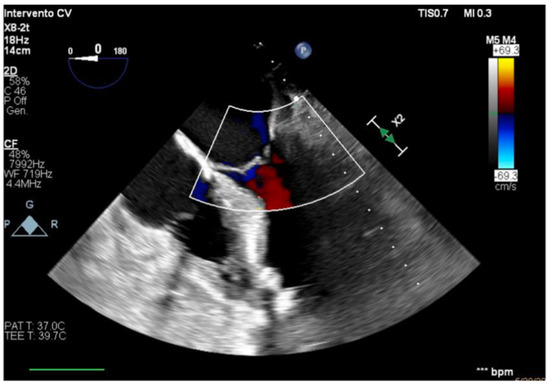

The transesophageal echocardiography showed LVOT-VTI 10 cm; apical, septal, and anterior wall akinesia; preserved function of the medium-basal segments of the inferior and lateral walls (Figure 3, Figure 4 and Figure 5); and RV-FAC 39% with an unloaded right ventricle (Figure 6).

Figure 3. TG mid-papillary level, the day after surgery (T0).